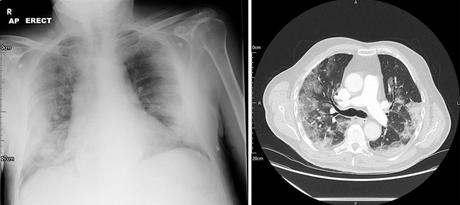

A pesar de los grandes cambios inflamatorios en los pulmones, que pueden ser evidentes radiológicamente (ver imagen), la ventilación parece estar menos afectada que el intercambio de gases, lo que resulta en hipoxia severa (a menudo) sin hipercapnia (T1RF).